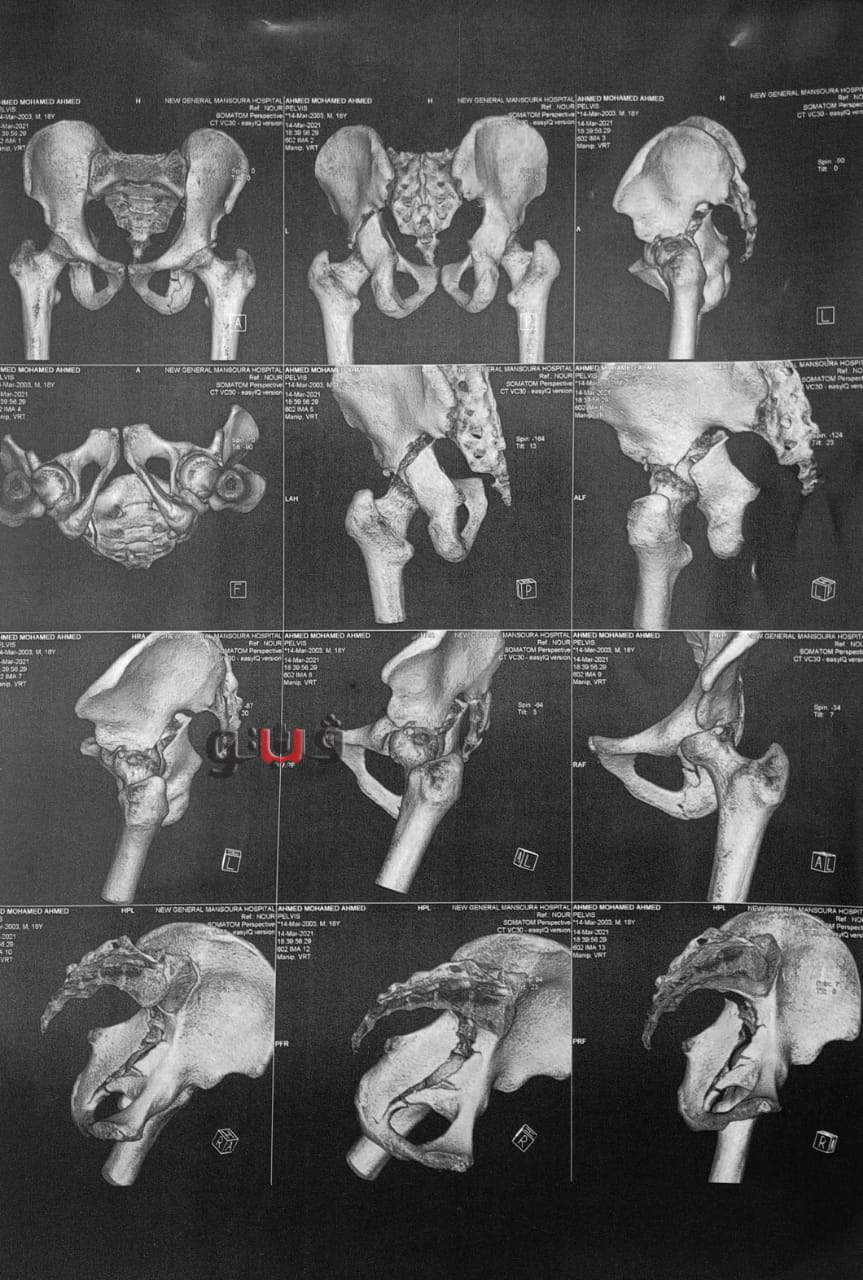

أعلن الدكتور سعد مكي وكيل وزارة الصحة بالدقهلية عن نجاح فريق طبي في إنهاء معاناة شاب يبلغ من العمر 20 عاما كان يعاني من كسر بحق مفصل الفخذ الأيسر مع خلع بالمفصل مع تأثر العصب الوركي وتمكن الفريق الطبي من إجراء جراحة عاجلة لرد الخلع وتثبيت الكسر بشرائح ومسامير معدنية وعمل استكشاف للعصب الوركي.